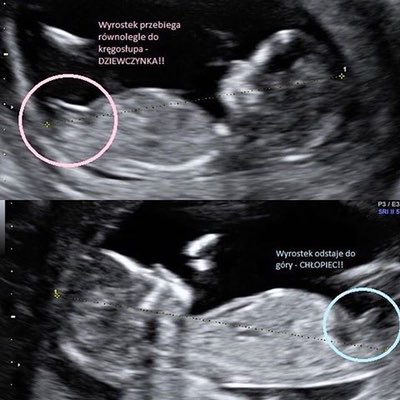

Hej dziewczyny, ja wprawdzie termin mam na 28 sierpnia ale jakoś tak bliżej mi terminem porodu do Was niż do większości sierpniówek dlatego tak u Was tu od jakiegoś czasu goszczę[emoji4]to moja druga ciąża, w domu już czteroletni synek[emoji4]mam do Was pytanie. Byłam dzisiaj na wizycie u mojej Pani ginekolog. I w trakcie badania obie w tym samym czasie dostrzegłyśmy między nóżkami Dzidziusia... siusiaka! Był naprawdę mocno zauważalny i wyglądał jak odrobinę krótsza trzecia noga. Pani doktor zaczęła się śmiać że powiększy się mój męski świat. Ja bardzo bym się ucieszyła,ale obecnie jestem w 11+1 i szczerze nie jestem przekonana czy na tym etapie można cokolwiek powiedzieć na temat płci. Jakie są Wasze doświadczenia w tym temacie?

Mój lekarz też mówi płeć na prenatalnych ale raczej nie po genitaliach tylko po jakiejś kości to stwierdza czy coś . Któraś dziewczyna tu pisała jak się ta metoda nazywa .U mnie lekarka określiła płeć na prenatalnych w poprzedniej ciąży, to było mniej więcej 12+3, wiec w sumie tydzień później niż u Ciebie. Podobno chłopców łatwiej zauważyć![]()

myślę, że pewnie chłopczykHej dziewczyny, ja wprawdzie termin mam na 28 sierpnia ale jakoś tak bliżej mi terminem porodu do Was niż do większości sierpniówek dlatego tak u Was tu od jakiegoś czasu goszczęto moja druga ciąża, w domu już czteroletni synek

mam do Was pytanie. Byłam dzisiaj na wizycie u mojej Pani ginekolog. I w trakcie badania obie w tym samym czasie dostrzegłyśmy między nóżkami Dzidziusia... siusiaka! Był naprawdę mocno zauważalny i wyglądał jak odrobinę krótsza trzecia noga. Pani doktor zaczęła się śmiać że powiększy się mój męski świat. Ja bardzo bym się ucieszyła,ale obecnie jestem w 11+1 i szczerze nie jestem przekonana czy na tym etapie można cokolwiek powiedzieć na temat płci. Jakie są Wasze doświadczenia w tym temacie?